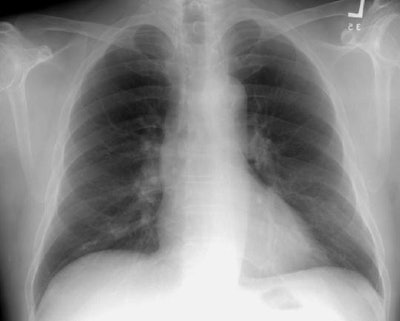

As is typical, the lesion in this case presents as a solitary pulmonary nodule within the right lower lung (it overlies the right anterior 5th rib on the PA exam, but is better seen on the lateral view). The lesion is well circumscribed and is non-calcified on computed tomography. There was no evidence of hilar or mediastinal adenopathy.